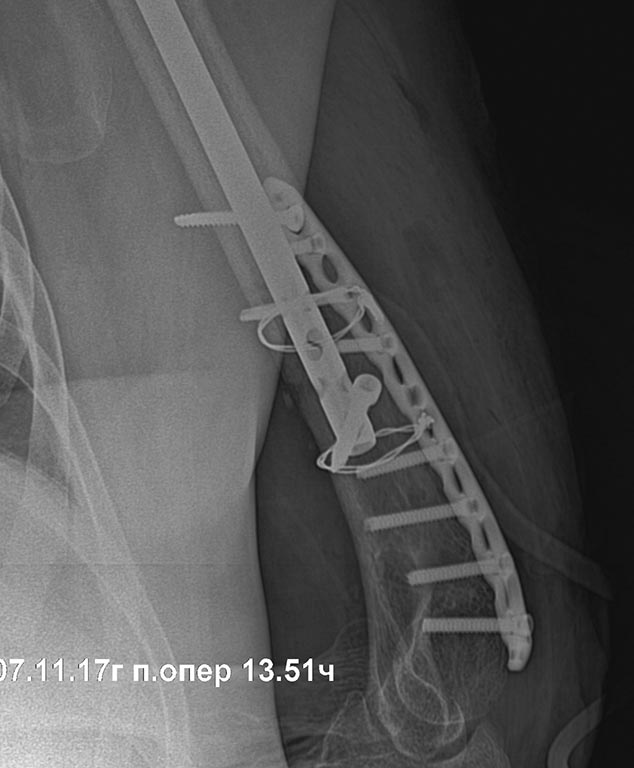

[Ortho] перелом плеча на гвозде

Rg